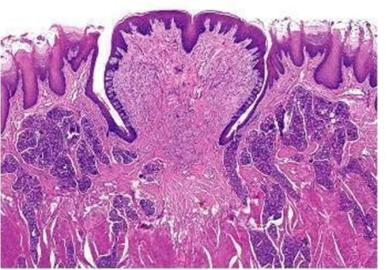

9. What structures are shown by the arrow and what is located in between them?

Explanation

The arrow is indicating the reticular ridges and connective tissue papillae in the skin. Rete ridges are the downward projections of the epidermis into the dermis, while connective tissue papillae are the upward projections of the dermis into the epidermis.